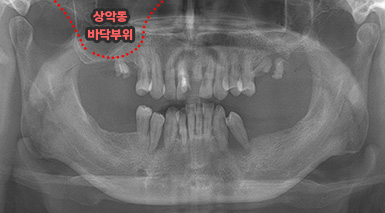

상악동 거상술

상악동은 윗턱뼈 내부의 구조물로서 개개인에 따라 생김새가 다릅니다.

상악동의 바닥이 잇몸뼈 방향으로 많이 내려온 경우, 임플란트를 식립하기에

잇몸뼈가 부족하게 됩니다. 이러한 경우 상악동 내부로 뼈이식을 하는

상악동 거상술이 필요하게 됩니다.

B

A